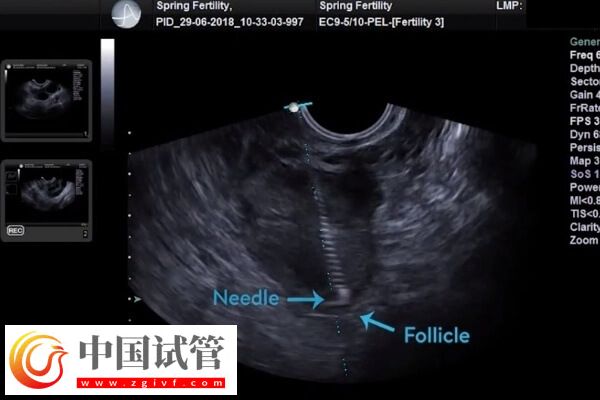

試管嬰兒診療中需要從卵巢內(nèi)把卵子取出來(lái),而因?yàn)槁殉泊倥乓院篌w積增大,部分患者會(huì)出現(xiàn)腹水的現(xiàn)象,為了不影響后續(xù)胚胎的種植,很多人會(huì)比較擔(dān)心腹水的影響,以及腹水應(yīng)該如何處理。